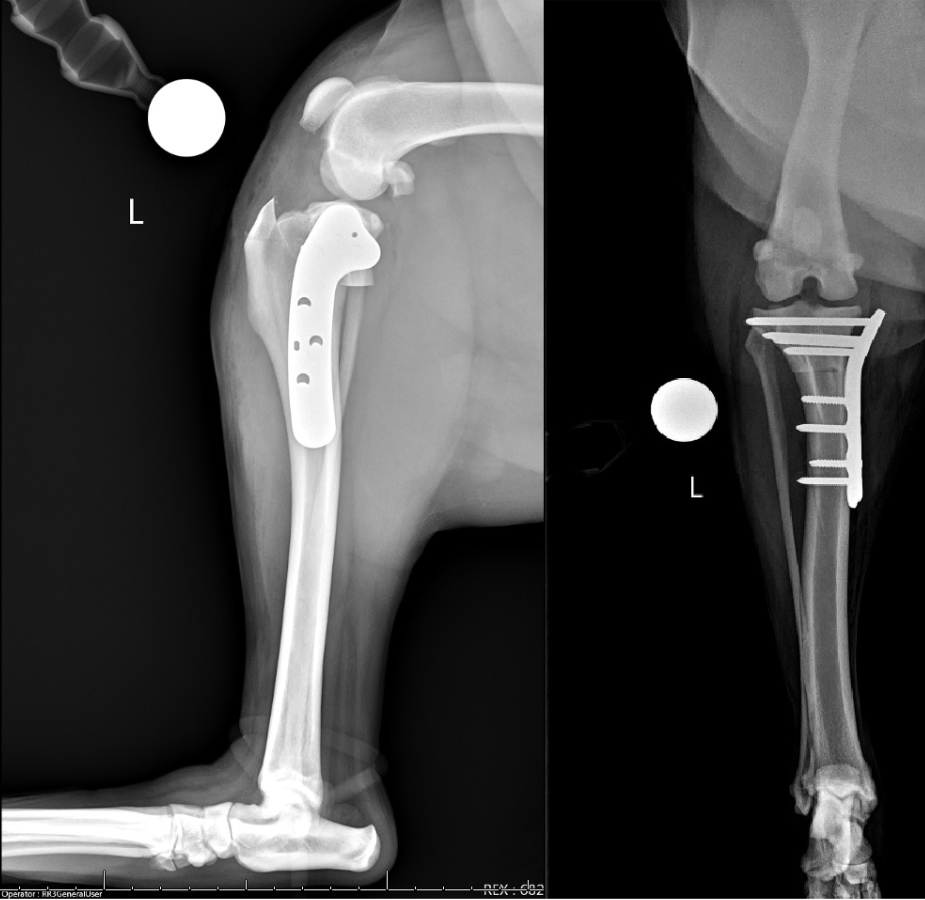

A routine TPLO was then performed and secured with a 3.5 mm broad, locking TPLO plate (VOI, Versiv). The tibial plateau angle (TPA) had been measured as 25 degrees on the preoperative radiographs. Postoperative radiographs revealed a TPA of 5 degrees consistent with the planned correction, good compression across the osteotomy site, and appropriate implant placement. Also note that the cranial tibial subluxation has been resolved (Figure 8).

Figure 8

The patient recovered routinely from anesthesia and surgery and was discharged the following day. The owners elected to pursue formal physical therapy with the GCVS Sports Medicine and Rehabilitation, as is routinely recommended following most orthopedic surgeries. The patient was evaluated at 8 weeks postoperatively, at which point the left hindlimb lameness had resolved and muscle atrophy had markedly improved. Palpation of the left stifle revealed a full and comfortable range of motion with mild crepitus noted. No discomfort was noted on direct palpation of the surgical implants, and cranial tibial thrust was absent. Consistent with the TPLO mechanism of function, the cranial tibial drawer remained moderate. No meniscal click was noted, and the patella tracked normally. Radiographs were performed and revealed complete osseous union of the previous osteotomy with mild bony callus formation at the caudal aspect. The implants remained static, and there was no evidence of implant-associated infection. Mild intracapsular soft tissue opacity (consistent with effusion) was noted. There was equivocal thickening of the patellar ligament near the insertion site on the tibia (Figure 9).

Figure 9